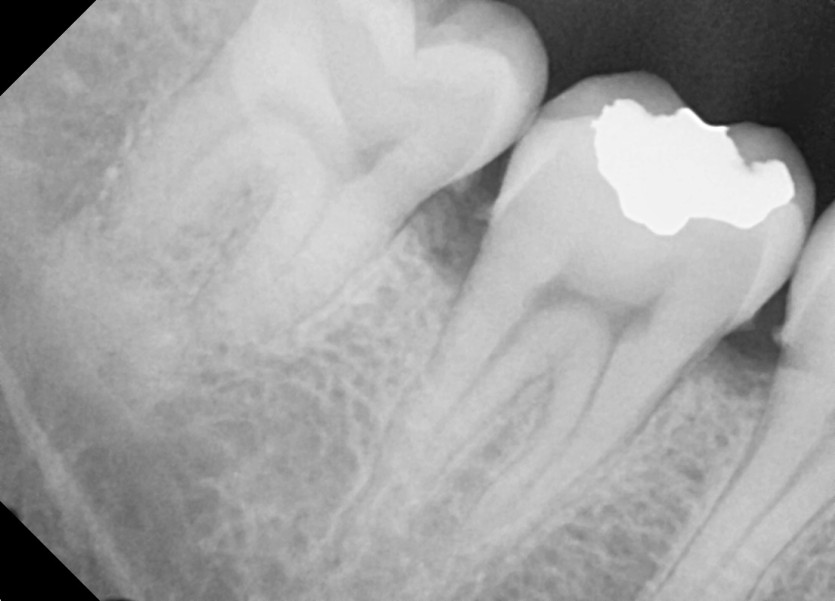

#38, 48 사랑니 발치

구강외과 전문의가 당일발치했습니다.